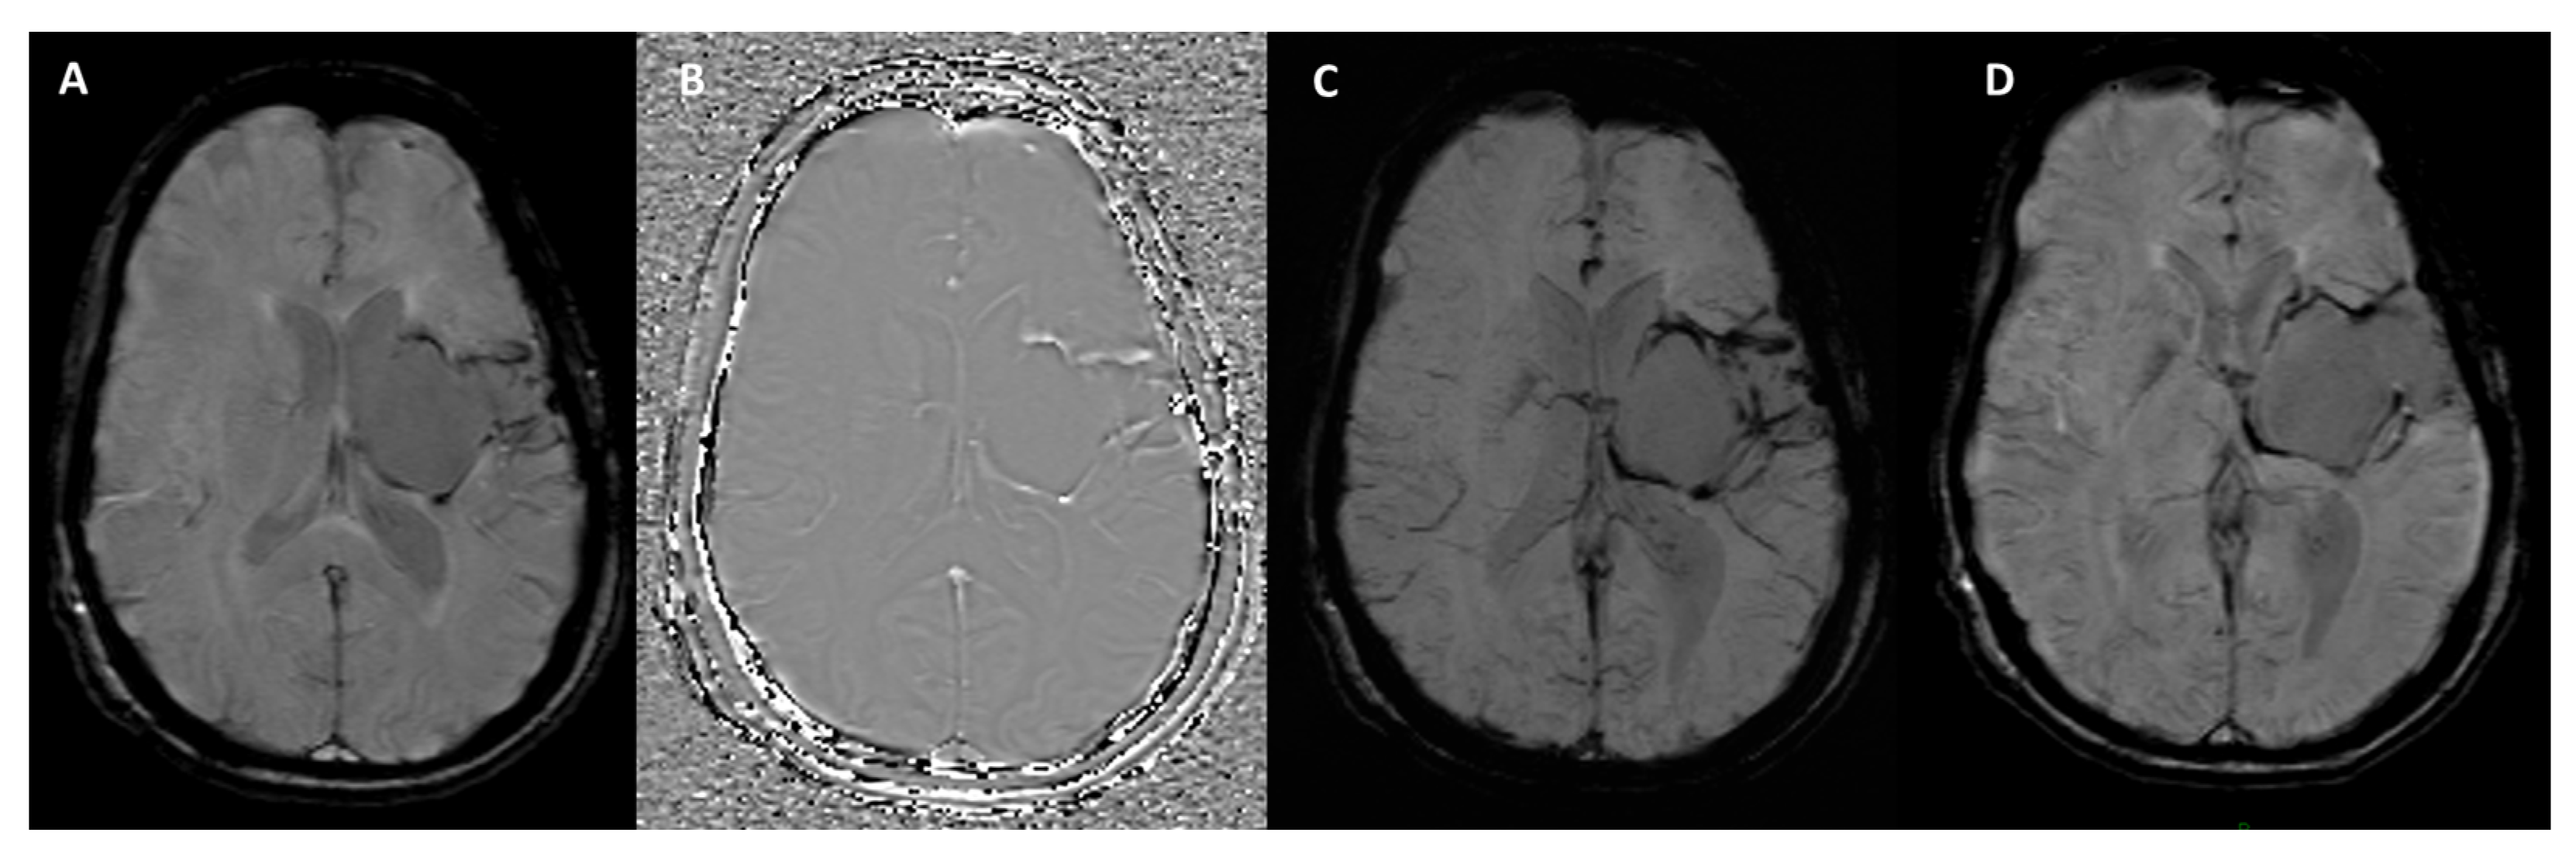

How Can Calcifications and Blood Be Differentiated on an SWI Phase Map?

- Wu, Z.; Mittal, S.; Kish, K.; Yu, Y.; Hu, J.; Haacke, E.M. Identification of calcification with MRI using susceptibility-weighted imaging: A case study. J. Magn. Reson. Imaging 2009, 29, 177–182. [Google Scholar] [CrossRef]